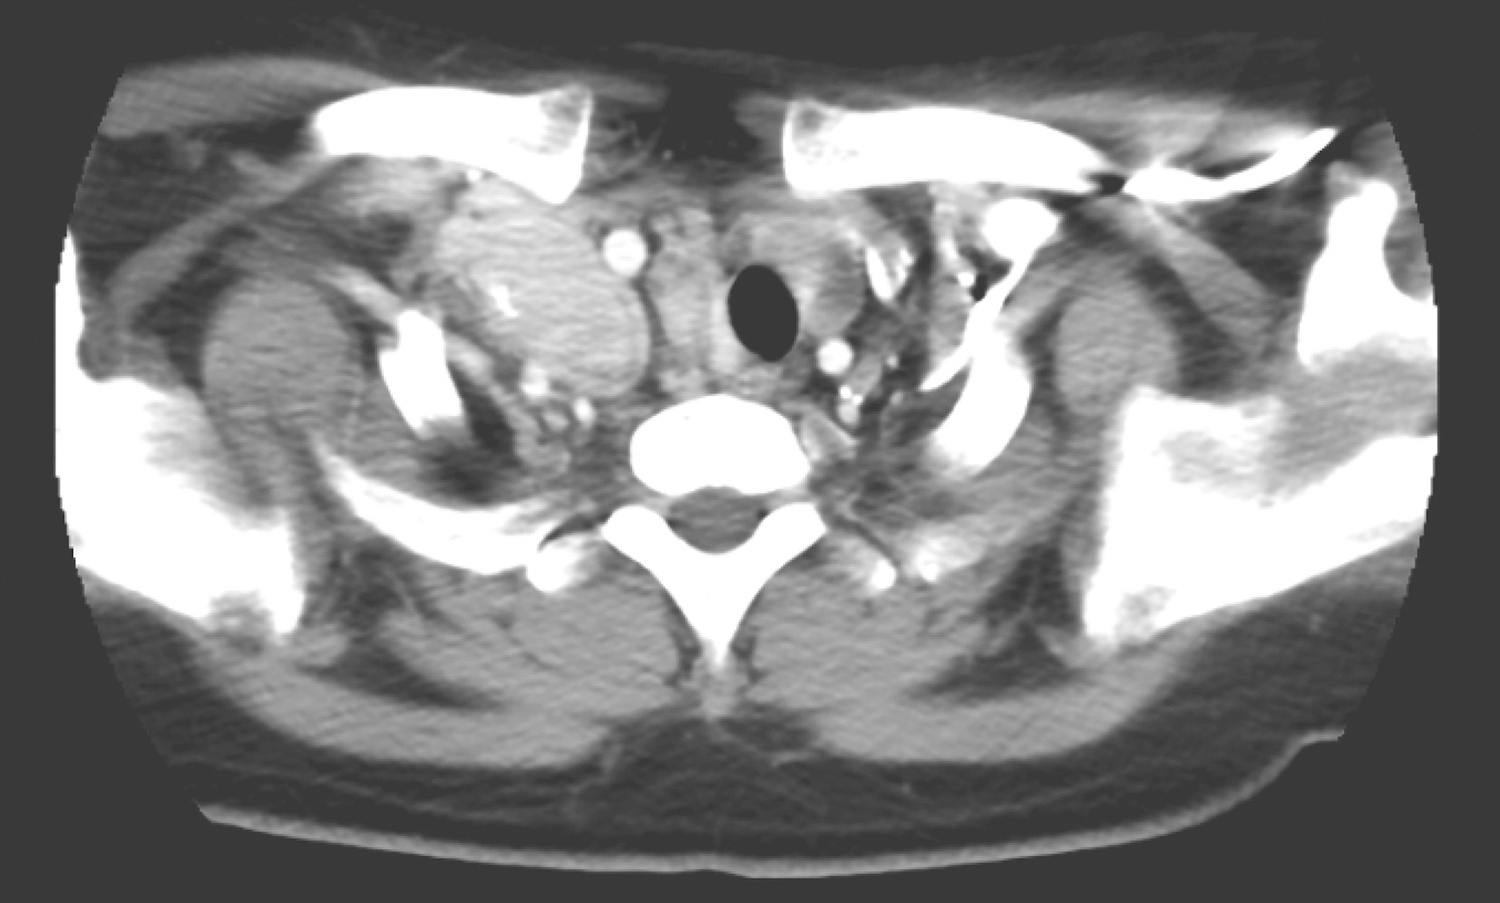

甲状腺弥漫不规则增大,密度不均匀,右叶为著,内有多发高、低密度结节影,大者最大截面约2.5cm×2.2cm,边界不清,增强扫描呈不均匀强化,向下伸入上纵隔胸骨后(图1);另见甲状腺左叶低密度结节,大小约1.6cm×1.0cm,不均匀轻中度强化。右侧颈部、锁骨水平及上纵隔区可见多发结节及肿物影,呈多结节融合状,最大截面约5.1cm×3.6cm,部分层面似与甲状腺右叶肿物相连续,包绕右侧颈动脉鞘,压迫右侧舌骨及下咽腔,增强扫描呈明显强化(图2)。双肺可见多发结节影,大者约1.9cm×1.4cm,边界清楚,明显强化(图3)。

图2 颈部增强CT示右侧颈部多发肿物包绕右侧颈动脉鞘